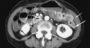

A B.C. woman who says half her large intestine was wrongly removed because of a misread CT scan is suing the local health authority and the unqualified radiologist who read the results.